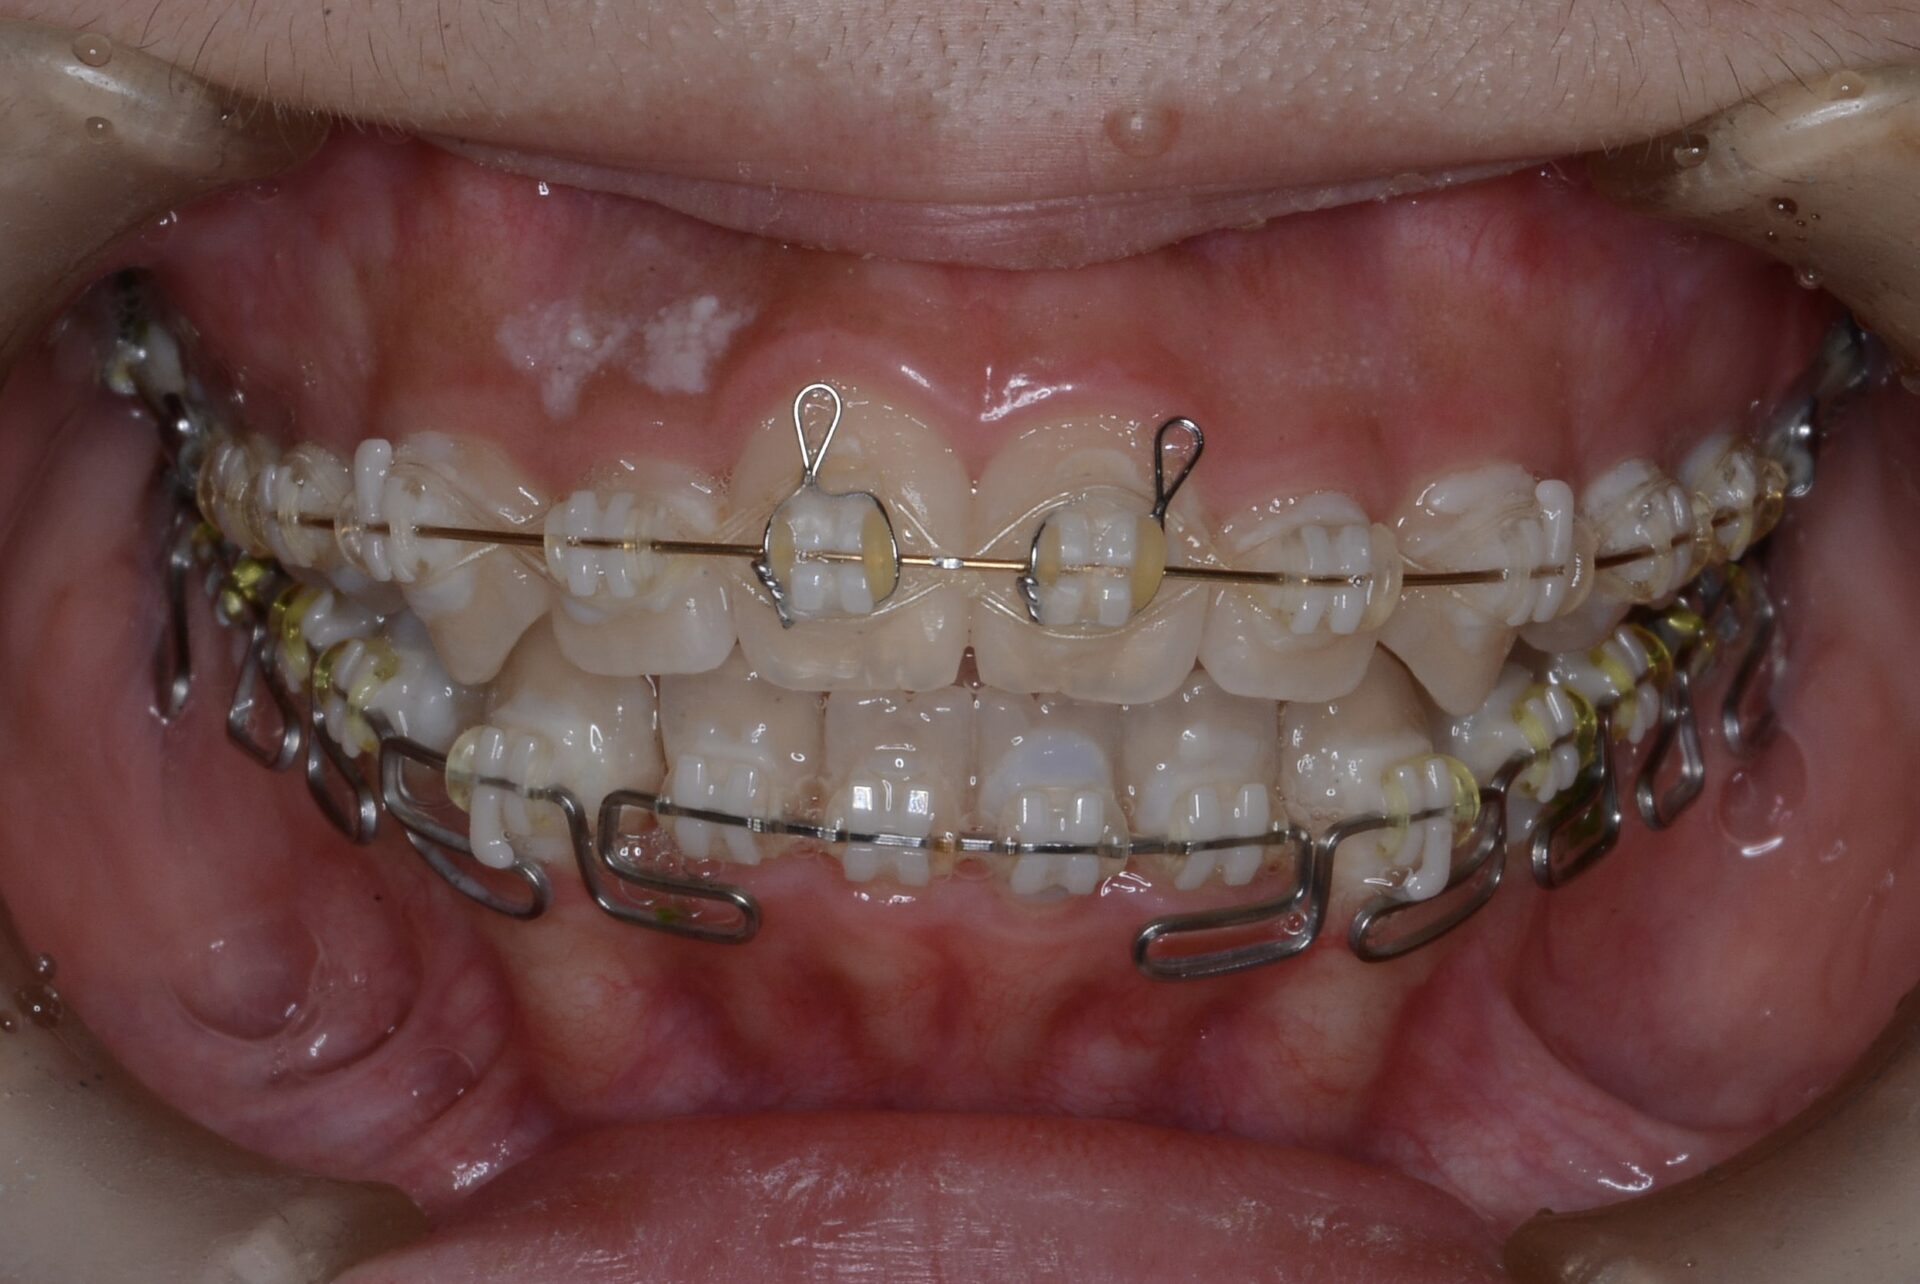

矯正治療スタート

矯正治療中

下顎臼歯部の圧下をするためのワイヤーをセットするもなかなか前歯は噛んでこない。